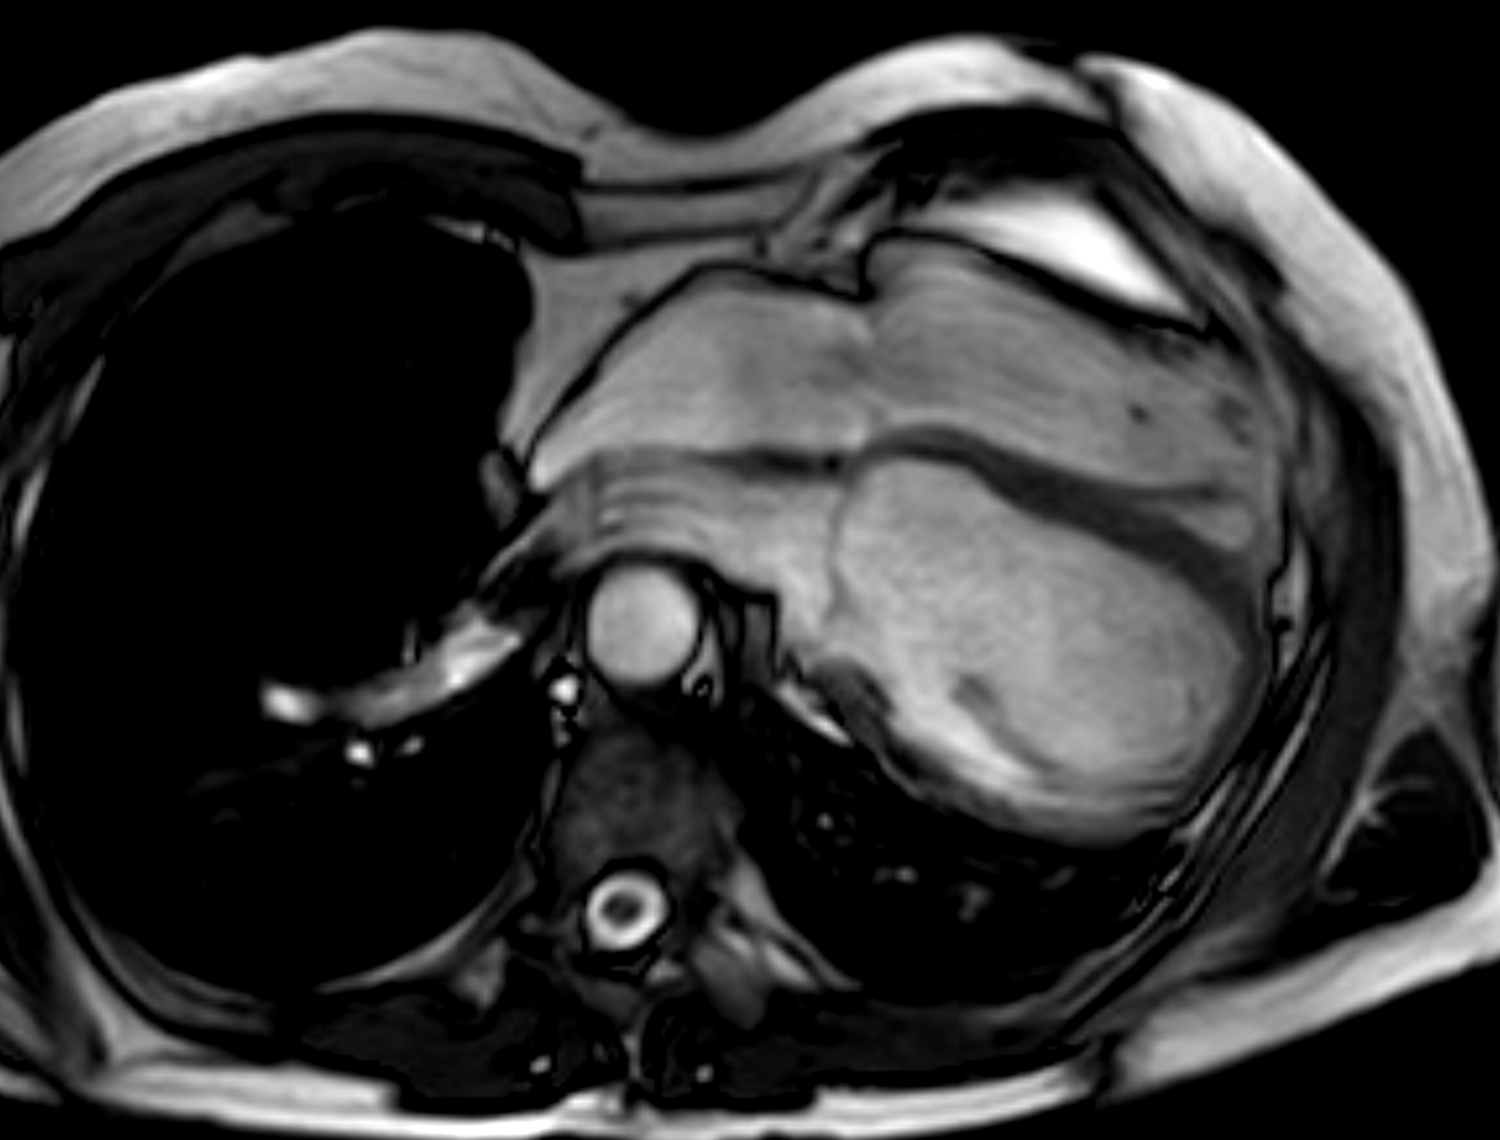

Fig. 4.Multi-modality imaging tissue characterization of pericardial cyst (arrows in all panels) adjacent to the right atrium. (A) Computed tomography axial slice, cyst was 10 Hounsfield units. (B) Magnetic resonance imaging (MRI) steady-state free precession bright blood sequence axial slice, cyst has increased signal. (C) MRI T2-short tau inversion recovery sequence, cyst has high signal. (D) MRI late gadolinium enhancement sequence axial slice, cyst has low signal.

MRI’s main advantage amongst imaging modalities is its ability in tissue characterization, and this is no different when applied to pericardial masses. Depending on tumor extension, the pericardium or myocardium may show thickening, or pericardial effusions, the latter often exudative or hemorrhagic with high signal intensity on T1-weighted sequences [31]. On T1-weighted, T2-weighted and gadolinium enhanced sequences, many tumors have low, high and high signal intensities [14, 31, 61, 62, 63]. Hemangiomas generally appear heterogeneous on all sequences, while lipomas have high signal intensity on all sequences, however its signal can be uniquely suppressed on fat-saturation pulse sequences. Fibroma have low vascularity and therefore have low signal intensity on T2-weighted sequence and none to minimal enhancement on gadolinium enhanced sequences. Mesotheliomas appear homogeneous on T1-weighted but have heterogenenous elevated signal on T2-weighte and gadolinium enhanced sequences. Of note, some studies have suggested heterogenous gadolinium uptake to indicate areas of increased lesion nodularity, growth and/or necrosis [64]. Pericardial cysts also appear as a well-circumscribed homogeneous mass with thin wall on MRI, displaying hypointense signal on T1-weighted sequence unless there is an exudative or hemorrhagic component, with hyperintense signal on T2-weighted sequence and no signal on LGE sequence (Fig. 4) [31, 65]. Lastly, pericardial hematomas show hyperintense, heterogeneous and hypointense signal on T1 and T2 weighted sequences in the acute, subacute and chronic stages, and no signal on LGE sequences regardless of timeframe [31].